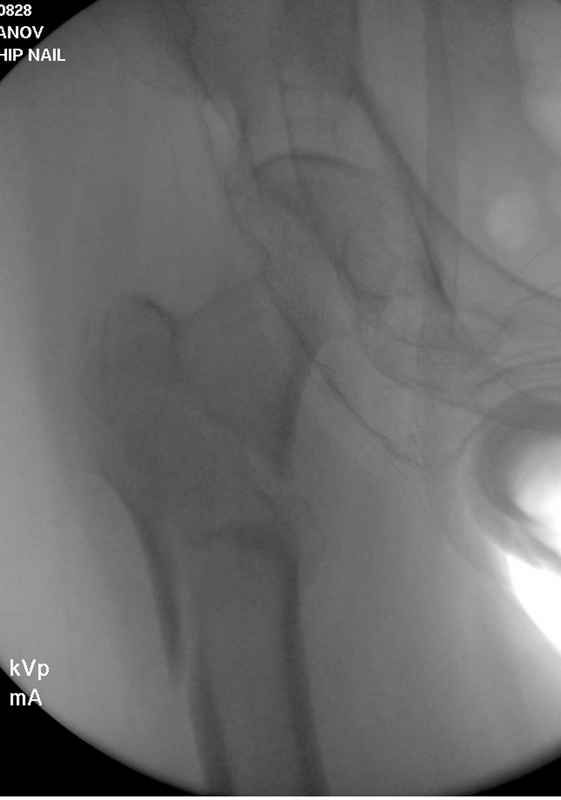

Re: Чрезвертельный перелом бедра

послал Djoldas Kuldjanov 25 Август 2009, 22:19

Здесь 83 года, травма в результате падения